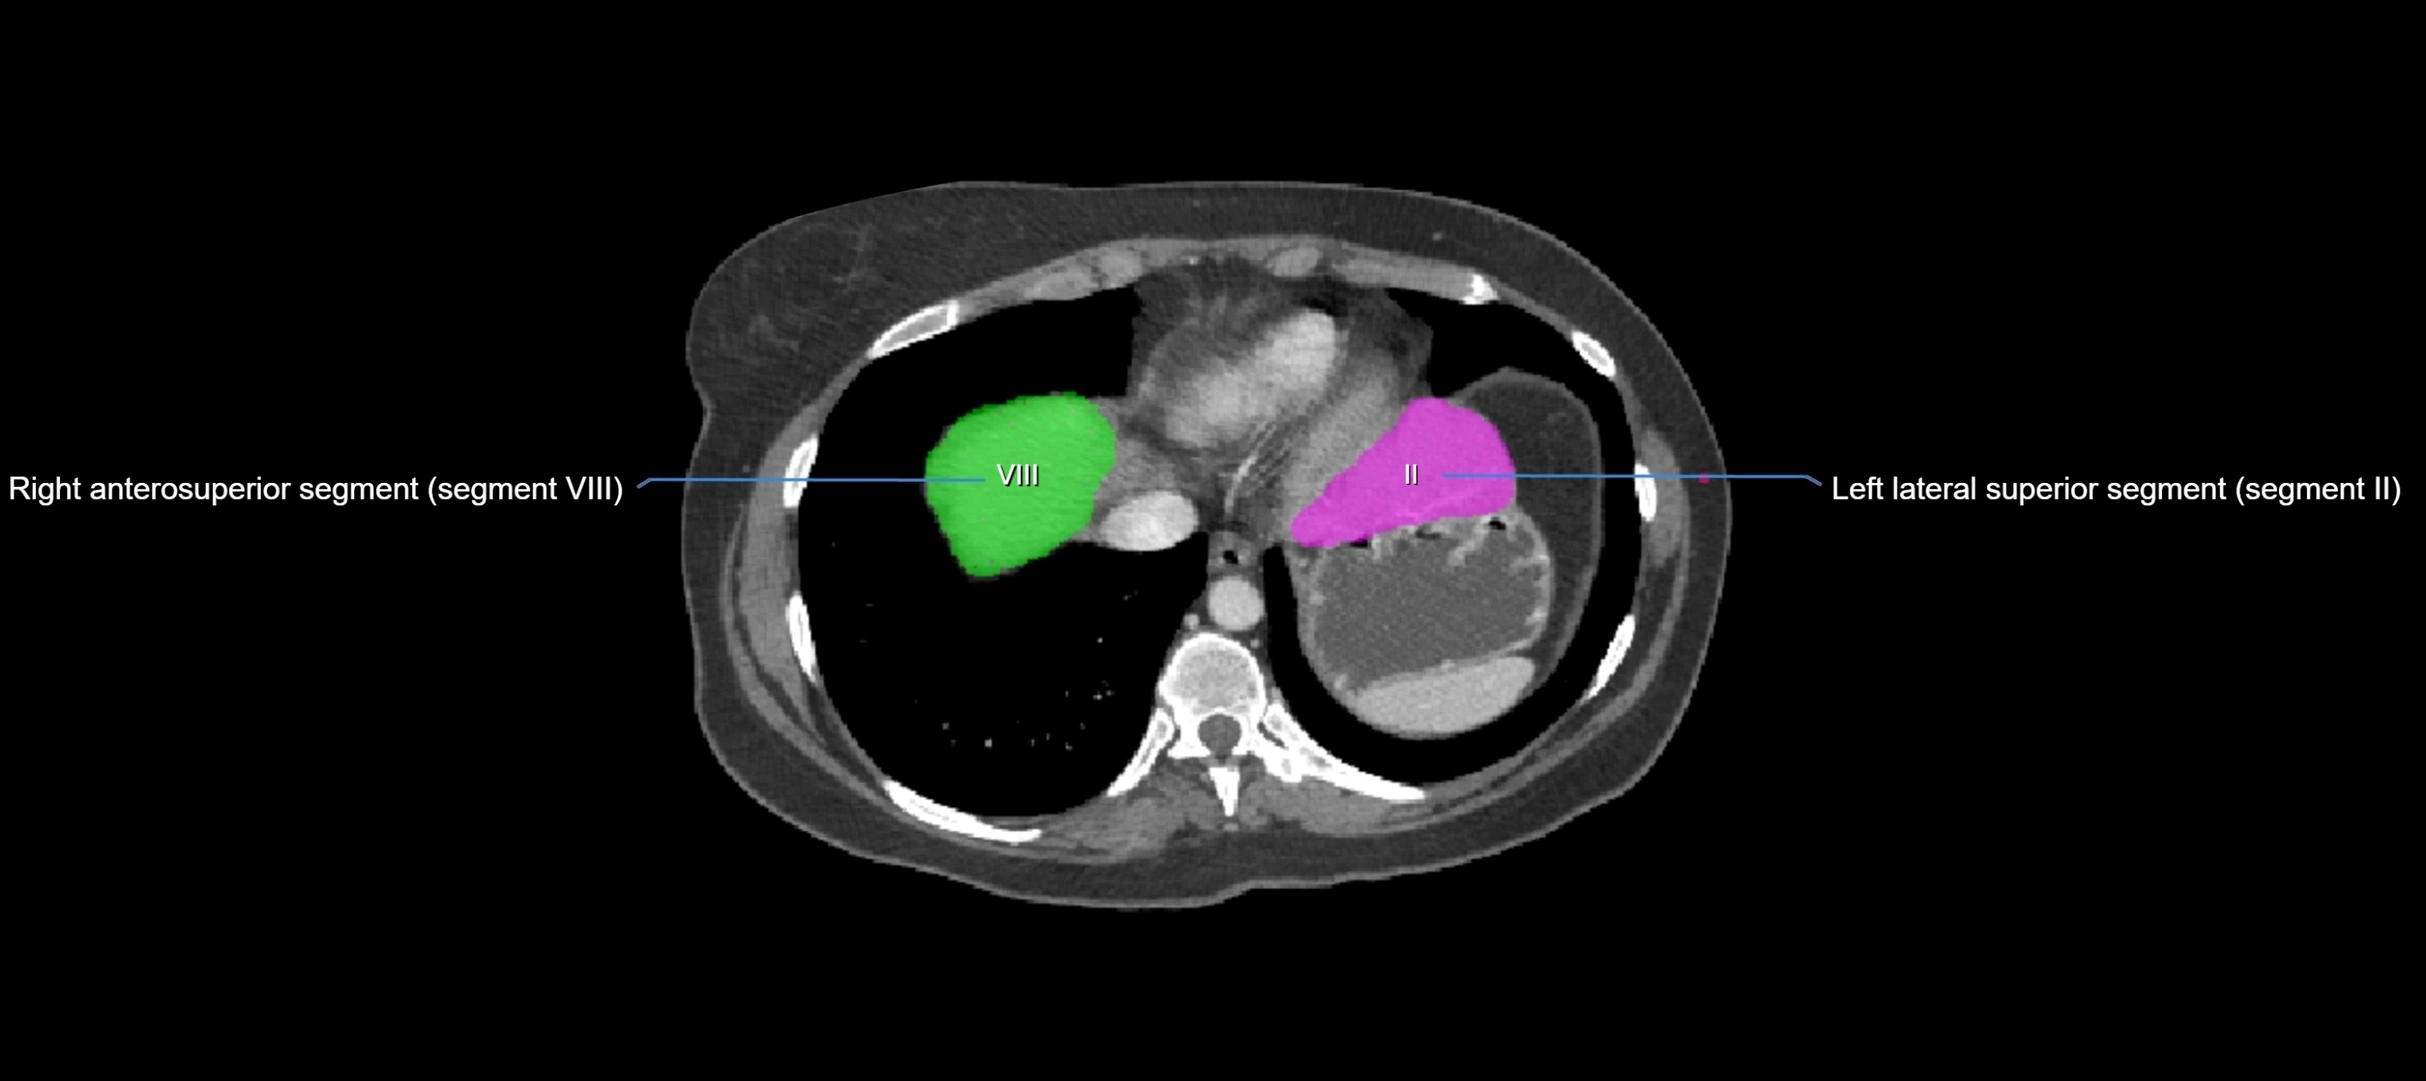

MRI image

image